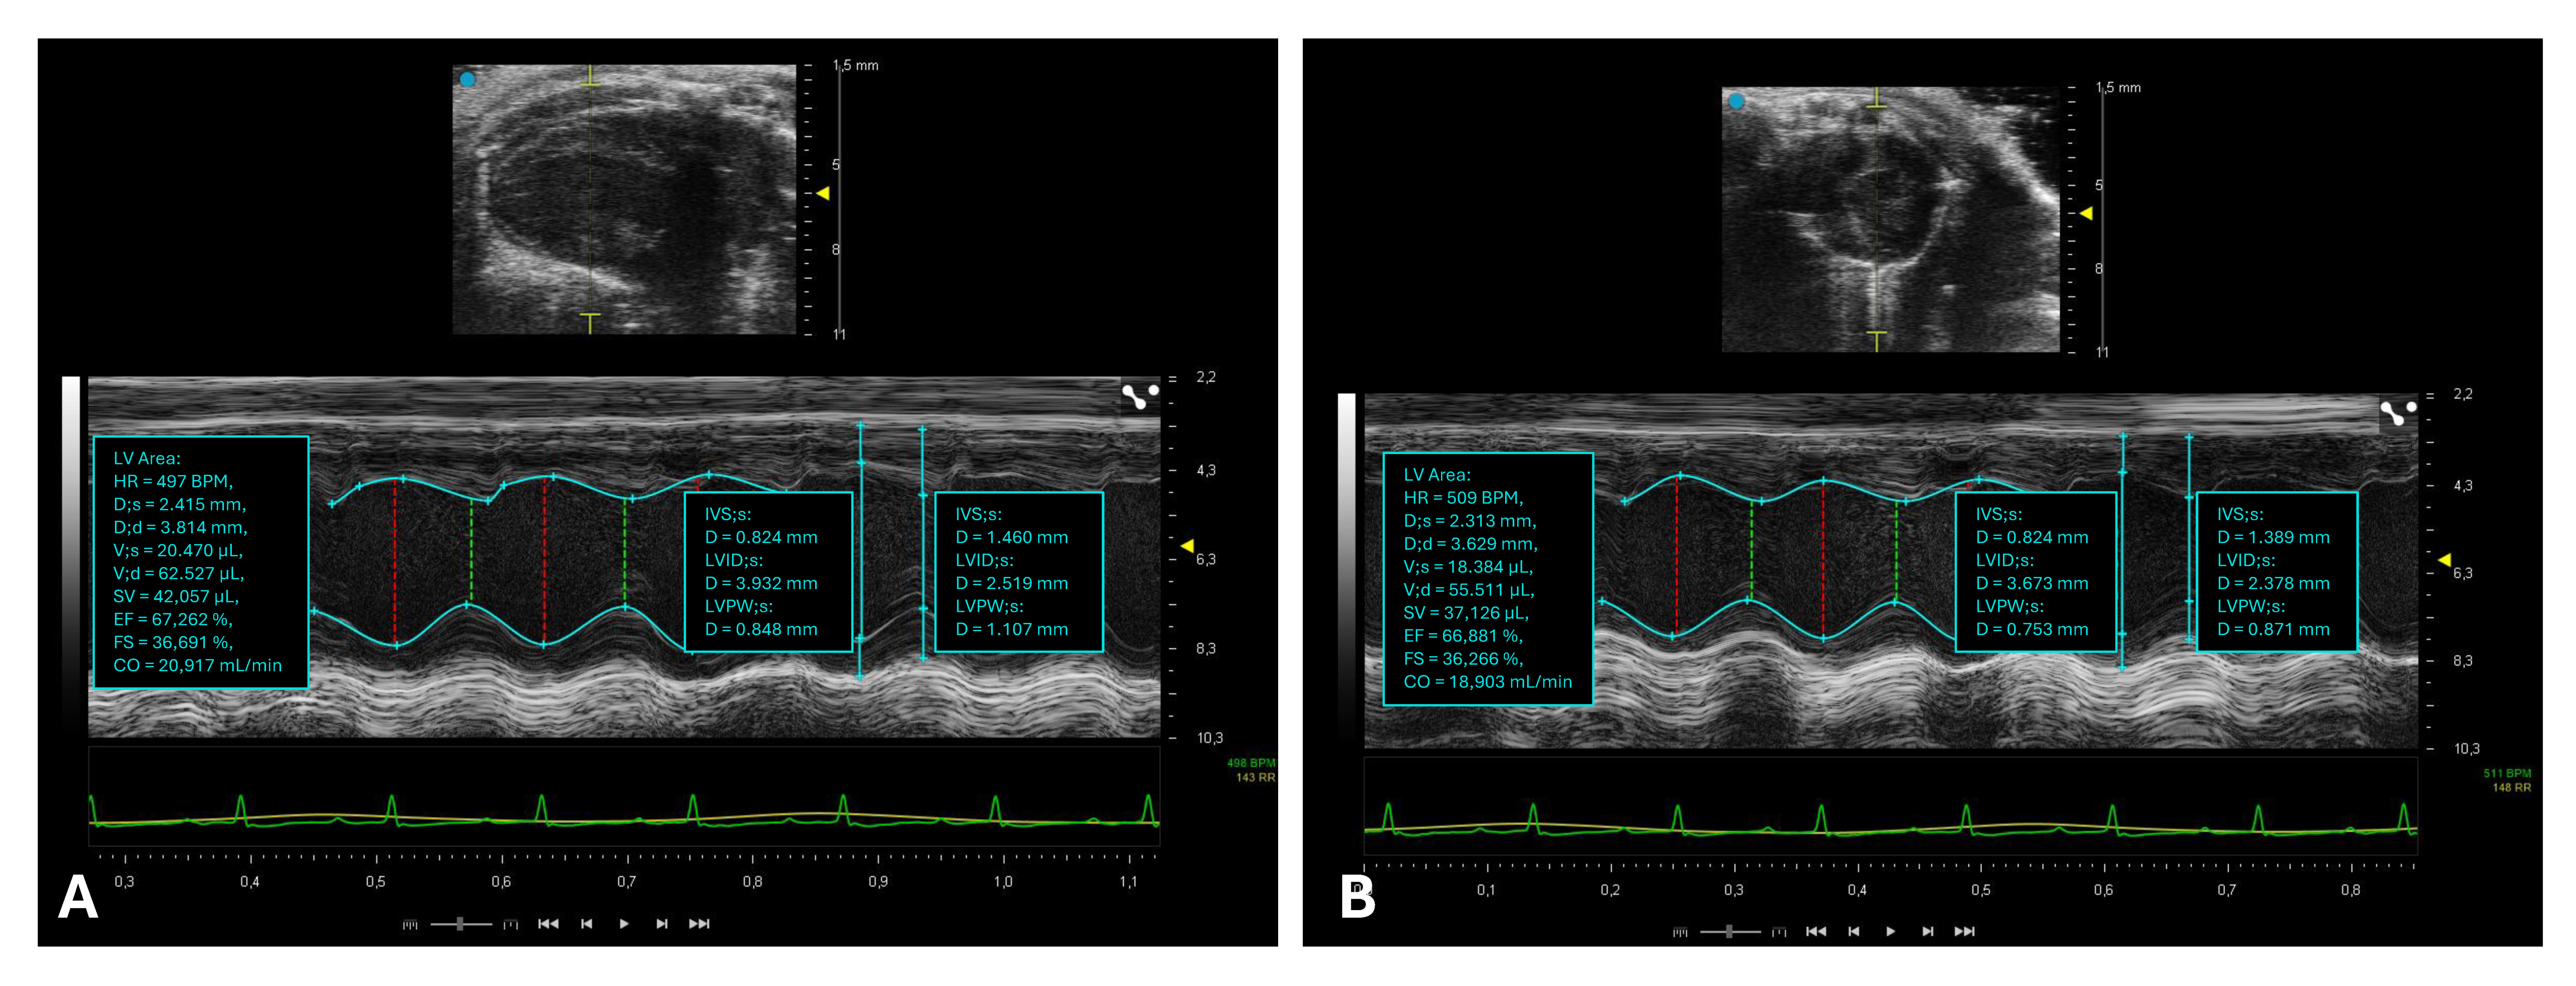

2.3. Assessment of Left Ventricular Systolic Function

2.4. Assessment of Left Ventricular Diastolic Function